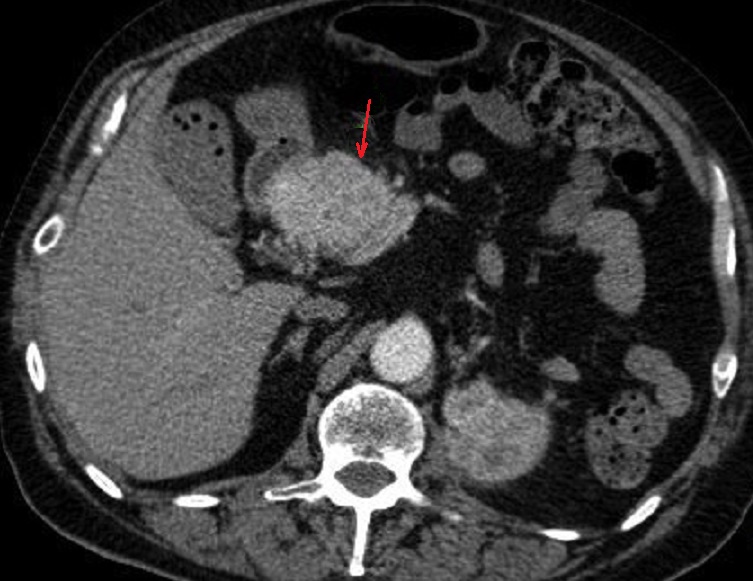

Image

radiologique TDM d'une adenocarcinoma de la tete du

pancreas en coupe axiale . Aspect lesionnel est un

masse hypodense a bord iregulier , l.a tete et le

corp du pancreas est deformation et tumefie .(

fleche rouge ) |

Parfois aspect lesionaire

est isodense ( fleche rouge ) . Par sa propiete de

moins de rehaussement de contrast intraveineuse

image radiologique du tumeur serait devenir nettete

sur les coupe TDM plus C+ . Image radiologique TDM

en coupe axiale ( n'a pas de contrast intraveineuse

) |